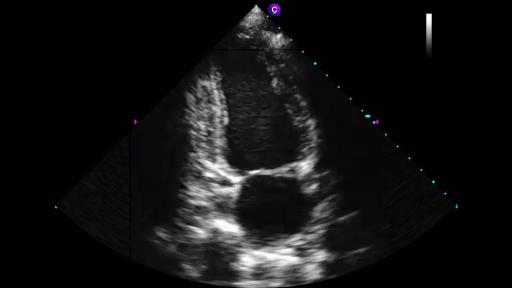

Caption Guidance™ uses artificial intelligence to empower medical professionals without specialized training to perform cardiac ultrasound.

BRISBANE, CA – February 7, 2020 – Caption Health, a leading medical AI company, announced today that the U.S. Food and Drug Administration (FDA) authorized marketing of Caption Guidance, software that assists medical professionals in the acquisition of cardiac ultrasound images. Caption Guidance uses artificial intelligence to provide real-time guidance and diagnostic quality assessment of images, empowering healthcare providers—even those without prior ultrasound experience—with the ability to capture diagnostic quality images. Empowering more clinicians with ultrasound image acquisition capability will bring the benefits of ultrasound to more patients, help standardize the quality of care, and help institutions realize valuable cost and time savings.

Caption Guidance was authorized via the De Novo pathway, a regulatory pathway reserved for novel technologies. The granting of this De Novo is groundbreaking, as Caption Guidance is the first medical software authorized by the FDA that provides real-time AI guidance for medical imaging acquisition. Caption Guidance is equipped with numerous features that together act as a co-pilot for clinicians when performing an ultrasound exam. The software emulates the guidance that an expert sonographer would provide to optimize the image, including providing real-time guidance on how to manipulate the transducer, and automated feedback on diagnostic image quality.

Marketing authorization was granted after the FDA reviewed extensive performance testing, including data from a pivotal multi-center prospective clinical trial conducted by Northwestern Medicine and Minneapolis Heart Institute at Allina Health, evaluating the use of Caption Guidance by registered nurses (RNs) with no prior ultrasound experience. Caption Guidance successfully met its primary endpoints, meeting the pre-specified criteria for study success.

In this study, eight RNs with no prior ultrasound experience used Caption Guidance to perform ultrasound exams on 240 patients, following a short training course. Patients were stratified to include a wide range of body-mass index and cardiac pathologies. The RNs acquired limited echo exams of 10 views each. Each exam was assessed by a panel of 5 expert cardiologists to determine if the exam was of sufficient quality to make a set of specific qualitative visual assessments.

Caption Guidance successfully met all four primary endpoints, meeting the pre-specified criteria for study success by acquiring images of sufficient quality for specific clinical assessments. Namely, the RNs successfully acquired limited echo exams for qualitative visual assessments of left ventricular size: 98.8%, 95% CI [96.7, 100]; left ventricular function: 98.8% [96.7, 100]; right ventricular size: 92.5% [88.1, 96.9]; and pericardial effusion: 98.8% [96.7, 100].